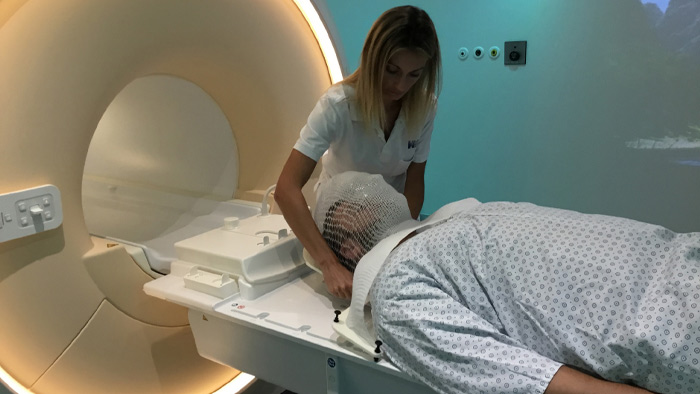

Epidermoid carcinoma of the left tongue base

The patient was diagnosed with an epidermoid carcinoma of the base of the left invading the amygdala lodge and the amygdaloglossal groove. Radiochemotherapy with curative aim was prescribed with a dose of 70 Gy for the tumor, 66 Gy on the suspicious nodes and 56 Gy on the elective drainage areas - in 33 fractions.

Simulation imaging

T2W 3D, 3D STIR and mDIXON MRI scans.